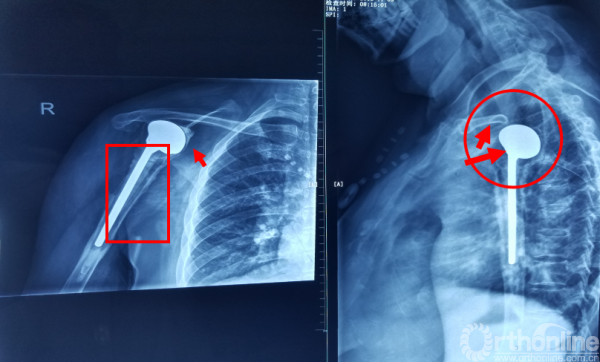

肩关节置换后11年松动合并感染

第一次手术术中无透视或者不仔细,造成病人长期的痛苦。第二次手术没有看到片子无法评论。现在病人明显是假体周围感染,鉴于术后11年,血源性感染可能性更大。病人假体周围骨溶解和肩关节脱位既有感染的因素,也有长期磨损的因素,具体只有详细询问病史才能明确。一期翻修只有查出明确病原菌和敏感抗生素的情况下才可行,否则都应该一期清创抗生素骨水泥况置,二期翻修。肱骨缺损问题不大可以通过使用加长柄假体。关键问题在于肩胛盂骨缺损,由于肩袖已经瘢痕化,肩胛盂磨损严重,使用半肩置换术后假体位置必将同以前一样出于脱位位置。而使用全肩置换,肩胛盂缺损无法固定假体。反式肩关节虽然可以防止脱位,但是关键问题也是肩胛盂部件无法固定。可以预见术后病人肩关节功能不会太好,需要降低病人期望值。

二次入院时X线检查

X片:假体周围透亮带;骨溶解;骨膜新骨形成。铟白细胞骨扫描(更为精确)

注意事项: 肱骨头内移至喙突处,位于后内侧下方已有骨桥连接

关节盂正常结构消失,至喙突偏内侧部位,上方紧贴肩峰下,仍然有骨质可用!

1.关节盂正常结构消失,前倾增大。

2.紧贴喙突内侧

3.骨质菲薄

术后X线